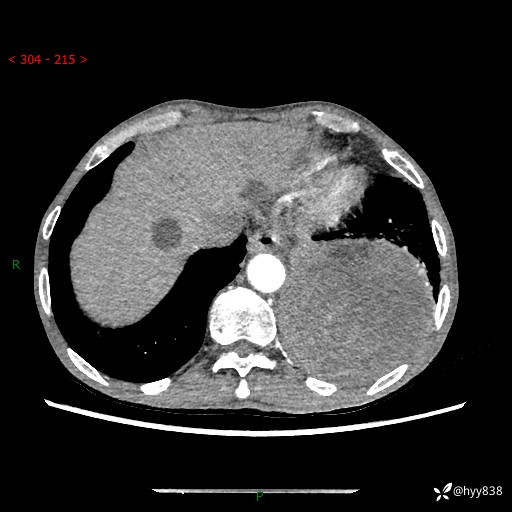

77岁/男,腹痛2月,CT发现左肺占位1天。巨大肿块,肺内或肺外来源…结果公布~

主诉:腹痛2月,CT发现左肺占位1天

现病史:患者于2025年9月间断左下腹胀痛,在当地镇卫生院行彩超检查考虑泌尿系结石,行止痛排石对症治疗未见明显好转;1天前腹痛症状加重,至当地市第三人民医院行CT检查:左肺下叶巨大团块状软组织影,考虑肿瘤性病变,建议增强CT检查;左侧胸腔积液;纵膈内淋巴结肿大;双肺肺气肿;右肺中叶纤维灶。为进一步求治,来我院就诊。

胸部CT平扫+增强